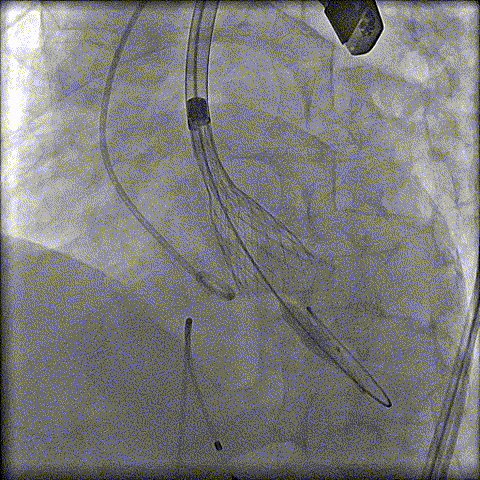

预扩

猪尾中部释放

稳定回收

评估

最终释放

后扩

无瓣周漏